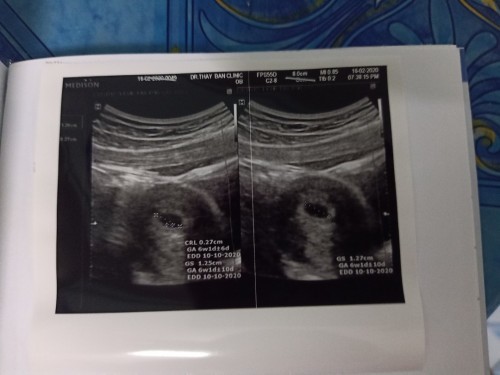

แม่ๆไปพบคุณหมอครั้งแรก ตอนตั้งครรภ์ได้กี่สัปดาห์ค่ะ? ตอนนี้ได้ 6 สัปดาห์ ไปพบคุณหมอ จะซาวเห็นลูกไหมคะ

ไปตอน6w หมอซาวด์เห็นแต่ถุงค่ะ 8wขึ้นไปถึงเห็นเด็ก

บ้านนี้ไปตอน6สัปดาห์คะเห็นเป็นถุงกลมๆแบบนี้ค่า

ไปตอน 6 w ซาวก็เจอเท่าเม็ดถั่วอะค่ะ